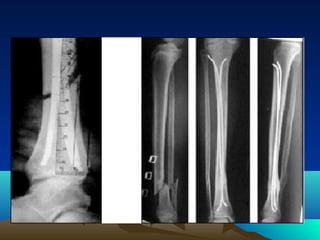

Cơ vùng cẳng chân

• Cẳng chân sau

– Lớp nông 3 cơ: cơ bụng chân,gan chân, cơ dép

– Lớp sâu 4 cơ: cơ chày sau, cơ gấp ngón chân cái dài,

cơ khoeo, cơ gấp các ngón chân dài.

• Cẳng chân trước 3 cơ: cơ chày trước, cơ duỗi

ngón cái dài,cơ duỗi các ngón chân dài

• Cẳng chân ngoài: cơ mác dài, cơ mác ngắn

Cơ vùng cẳngchân • Cẳng chân sau – Lớp nông 3 cơ: cơ bụng chân,gan chân, cơ dép – Lớp sâu 4 cơ: cơ chày sau, cơ gấp ngón chân cái dài, cơ khoeo, cơ gấp các ngón chân dài. • Cẳng chân trước 3 cơ: cơ chày trước, cơ duỗi ngón cái dài,cơ duỗi các ngón chân dài • Cẳng chân ngoài: cơ mác dài, cơ mác ngắn